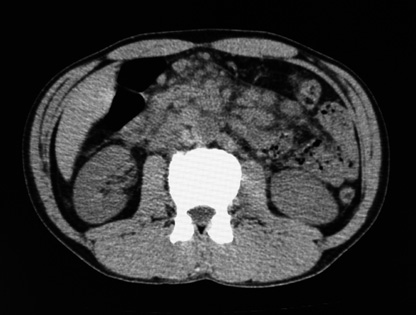

Adult T cell leukaemia/lymphoma, abdominal lymphadenopathy

ATLCT01.jpg

case 02: 50 year-old male.

突然発症した両季肋下痛で受診。BT37℃, CTで多数の腹膜リンパ節腫大を指摘される。ATLV-1陽性, sIL-2R 21100. LDH 465IU/L

CBC: WBC4800, RBC412x104;, ly18%, plt40x104;で, 末梢血に異常リンパ球の増殖はみとめられなかった。